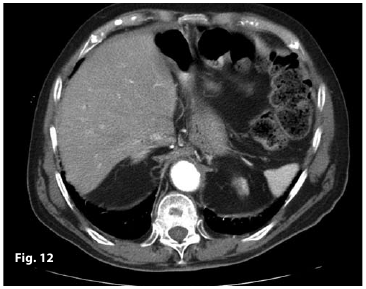

Figure11

Figure12

Figure13